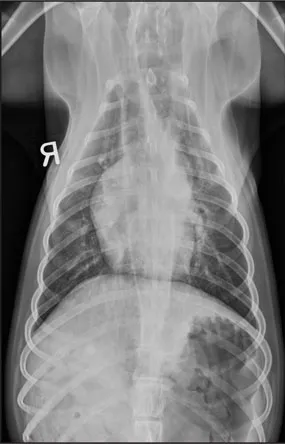

CASE 1.1 A 7-year-old neutered male Labrador Retriever who was hit by a car. You obtain these thoracic radiographs: Figs. 1.1a, b, left and right lateral projections, respectively; Figs. 1.1c, d, ventrodorsal and dorsoventral projections, respectively.

1.1c